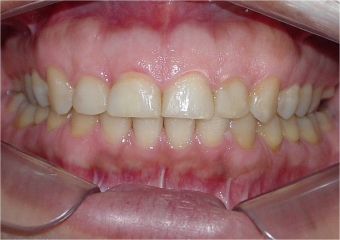

Mordida inicial